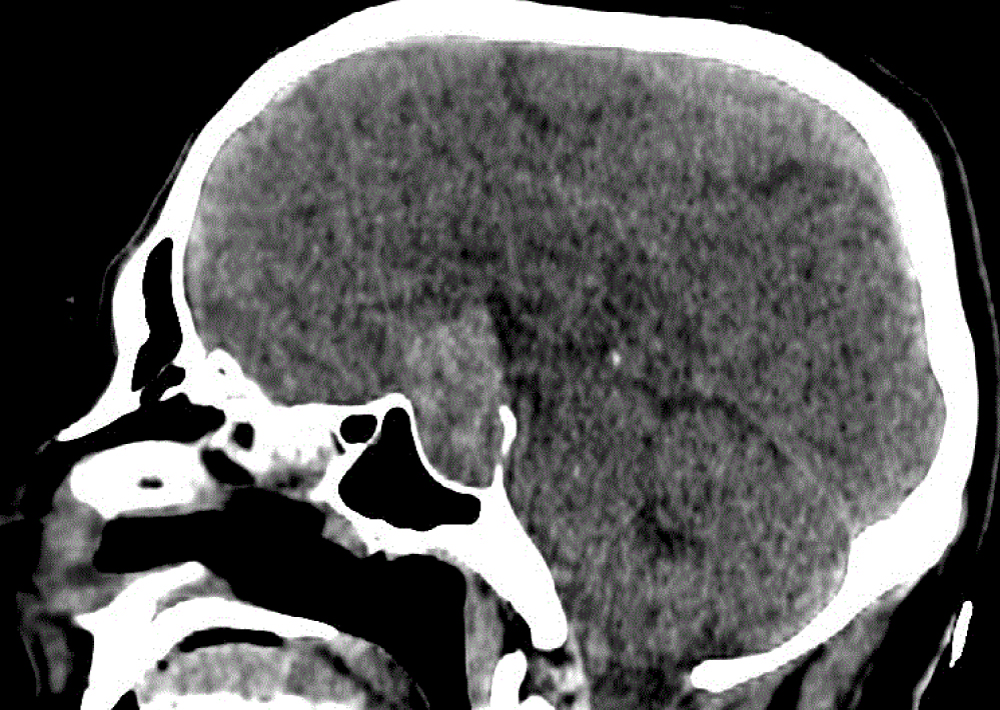

The plain cranial computed tomograghy (CT) scan done and demonstrated a large sellar and suprasellar with intrinsic hemorrahage mass lesion measuring 28 × 38 × 21 mm (Figure 1). The hemmorhagic pituitary mass made us thinking about Pituitary Apoplexy so we planned for cranial magnetic resonance ımaging (MRI). The cranial MRI with multiplanar and multi sequencies obtained specifically for the pituitary gland Pre-Post gadolinium contrast showed an enlarged sella turcica with large sellar and suprasellar heterogenous mass lesion showing figure of snowman in the coronal images (Figure 2).

Figure 1: Sagittal CT scan showing a large sellar and suprasellar with intrinsic hemorrahage mass lesion. View Figure 1